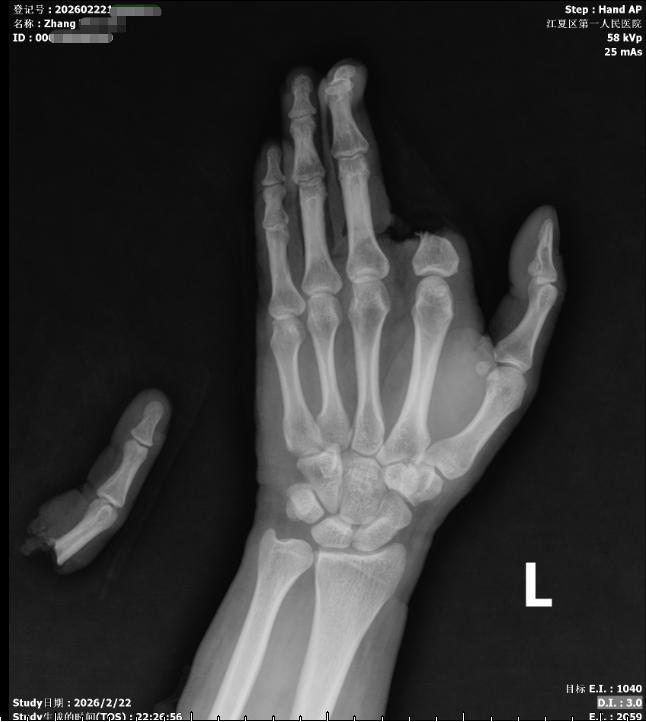

这场“生命竞速”始于2月22日(农历大年初六)晚。当晚10时35分,张先生被朋友紧急送入江夏区第一人民医院(协和江南医院)急诊科。医生发现其左手被电锯严重割伤,导致其左手食指自掌指关节处完全离断,仅少许皮肤相连;左手中环小指掌指关节处可见一约6cm横行伤口,活动性出血,创面软组织挫伤严重。“我当时脑子一片空白,就看见血不停地涌出来,心想‘这只手怕是要废了’。”据张先生回忆。

“对于完全离断的指体,缺血时间越短,再植成活率越高。我们必须争分夺秒,启动绿色通道,为再植争取最大的‘黄金窗口期’。”该院手外科主任陈冬生副主任医师表示,食指(示指)是进行精细操作和力量性抓握的关键,保住它,就是保住患者未来的手部功能与劳动能力。“在无明显手术禁忌证的情况下,我们连夜协调手术室,拟定在神经丛阻滞麻醉下进行‘左手示指再植及左手伤口清创缝合神经肌腱血管探查修复术’。”